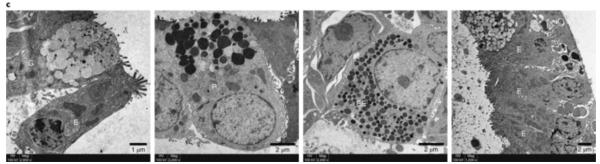

使用透射电子显微镜,研究者在分化的蝙蝠肠样中鉴定出具有四种主要肠道细胞类型特征的细胞,包括肠上皮细胞(E),杯状细胞(G),潘式细胞(P)和肠内分泌细胞(EE),如下图所示:

尽管有一条蝙蝠小肠类器官连续扩增了12周,但其他四条蝙蝠小肠类器官在4或5周后就停止了活性增殖,可作参照的是,人的肠类器官可以连续扩展至少1年。尽管如此,研究者还是建立了第一个模拟蝙蝠肠上皮细胞组成的蝙蝠肠类器官。